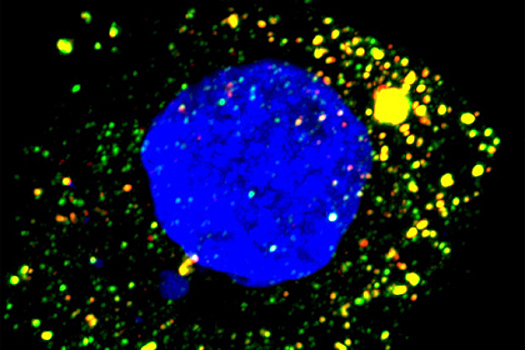

Ученые выяснили, что вирусу гепатита для репликации требуются нуклеотидилтрансферазы TENT4A и TENT4B — ферменты, которые осуществляют присоединение фосфорных групп к нуклеотидам. Кроме того, оказалось, что гепатит А нуждается в белке ZCCHC14, связывающемся с определенной частью РНК вируса гепатита А. В результате вирус приобретает способность использовать TENT4 для репликации собственного генома.

Таким образом, если заблокировать рекрутирование ферментов TENT4 вирусом, можно остановить репликацию патогена и, как следствие, развитие заболевания. В качестве потенциального препарата исследователи протестировали соединение RG7834, которое активно блокирует размножение другого вируса — вируса гепатита В. В статье, опубликованной в PNAS, авторы подробно описали влияние перорального RG7834 на развитие инфекции в печени. Препарат резко снижал способность вируса повреждать печень у мышей, которые были генетически уязвимы для гепатита А.